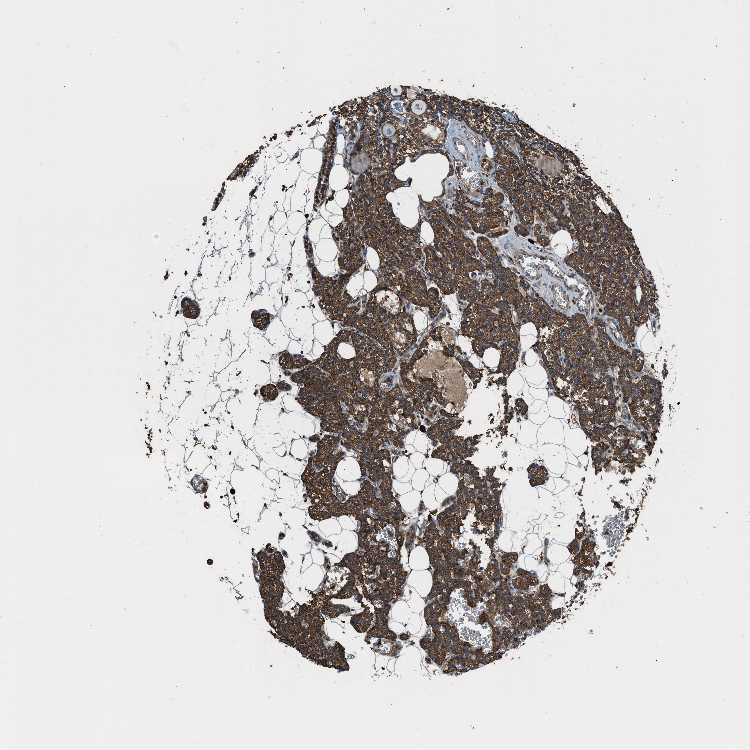

TISSUE PRIMARY DATA PARATHYROID GLAND Show tissue menu

PARATHYROID GLAND - Antibody stainingi

Antibody staining in the annotated cell types in the current human tissue is reported as not detected, low, medium, or high, based on conventional immunohistochemistry profiling in selected tissues. This score is based on the combination of the staining intensity and fraction of stained cells.

Each image is clickable and will lead to virtual microscopy that enables deeper exploration of all samples and also displays staining intensity scores, fraction scores and subcellular localization as well as patient and tissue information for each sample.

Antibody HPA017962Antibody CAB005120

Glandular cells HighHigh